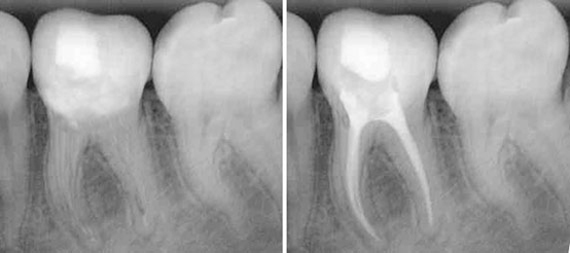

Очень важно обработать всю длину корневого канала. Для контроля делают рентген. После очищения каналов стоматолог помещает в них лекарство и закрывает временной пломбой, чтобы защитить от попадания инфекции. Постоянную пломбу сразу не ставят. Сначала нужно вылечить зуб, устранить воспаление и предотвратить развитие осложнений.